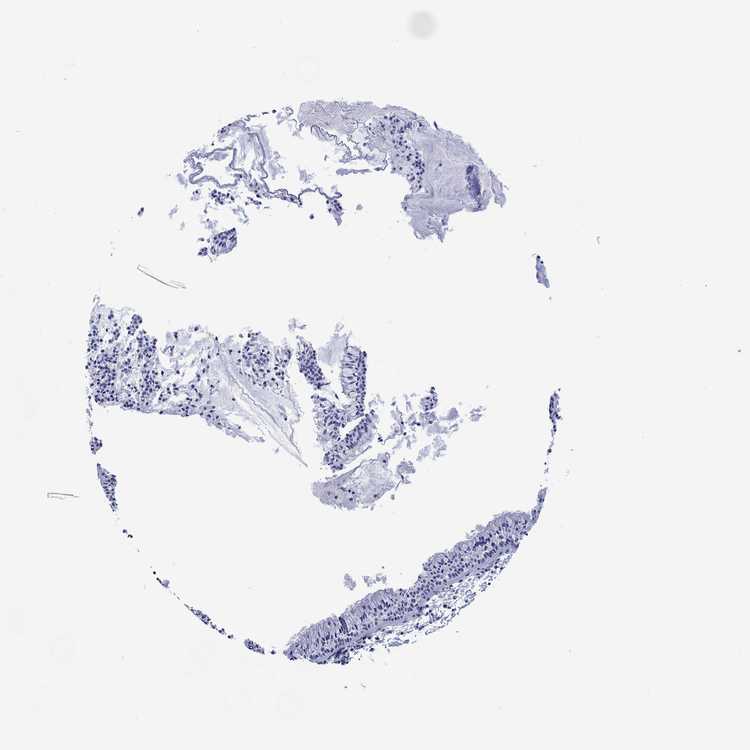

NASOPHARYNX - Antibody stainingi

Antibody staining in the annotated cell types in the current human tissue is reported as not detected, low, medium, or high, based on conventional immunohistochemistry profiling in selected tissues. This score is based on the combination of the staining intensity and fraction of stained cells.

Each image is clickable and will lead to virtual microscopy that enables deeper exploration of all samples and also displays staining intensity scores, fraction scores and subcellular localization as well as patient and tissue information for each sample.

Antibody HPA074923Antibody HPA075573

Respiratory epithelial cells Not detectedLow